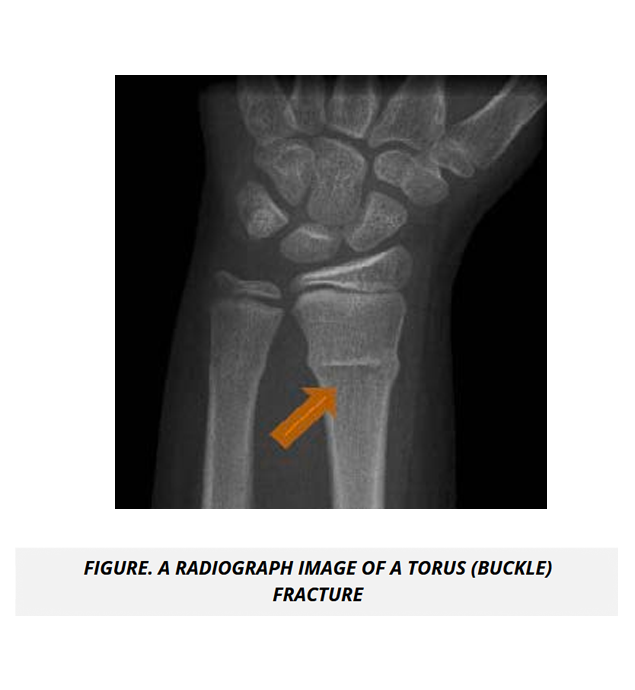

The UMock USMLE® Step 1 prep course features high quality pathologic images, gross and microscopic views, as well as radiologic imaging illustrating key concepts, disorders, and abnormal processes to help you gain a complete understanding of subject material.

The course features detailed tables and high quality radiologic and gross images to help you conceptualize the application of medicine for normal and abnormal body system processes and pathologies in rheumatology and the musculoskeletal system.

In Embryology, the UMock USMLE® Step 1 prep course presents high-yield content in a concise format that helps you understand and quickly recall concepts in human development and congenital malformations, and apply the connection between embryological knowledge and clinical medicine. The course further clarifies key facts and concepts to help you maximize comprehension and visual understanding in applying concepts with high quality diagnostic, radiographic, and clinical images.